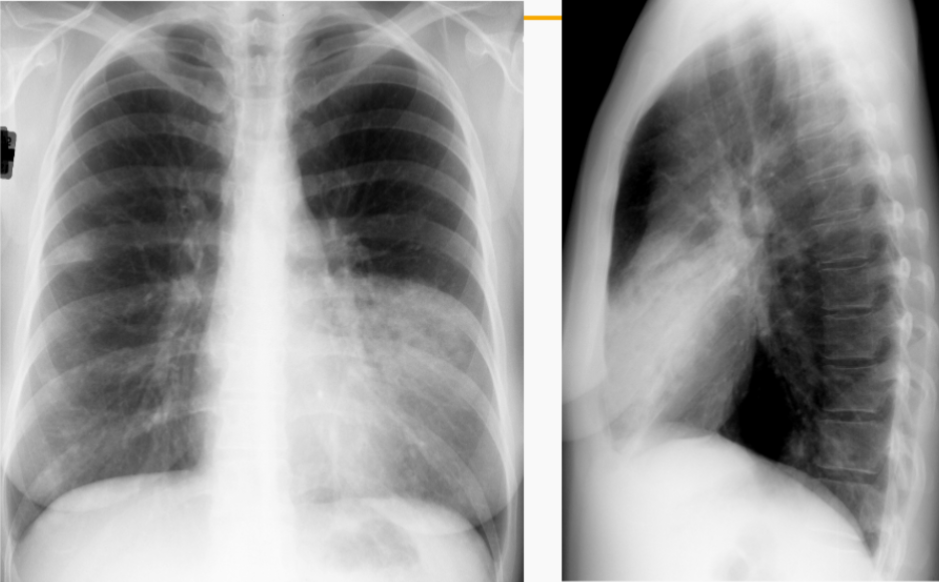

What is this patient presenting with?

Pneumothorax

(tip: look for THIN pleural line with absent lung markings beyond its border)